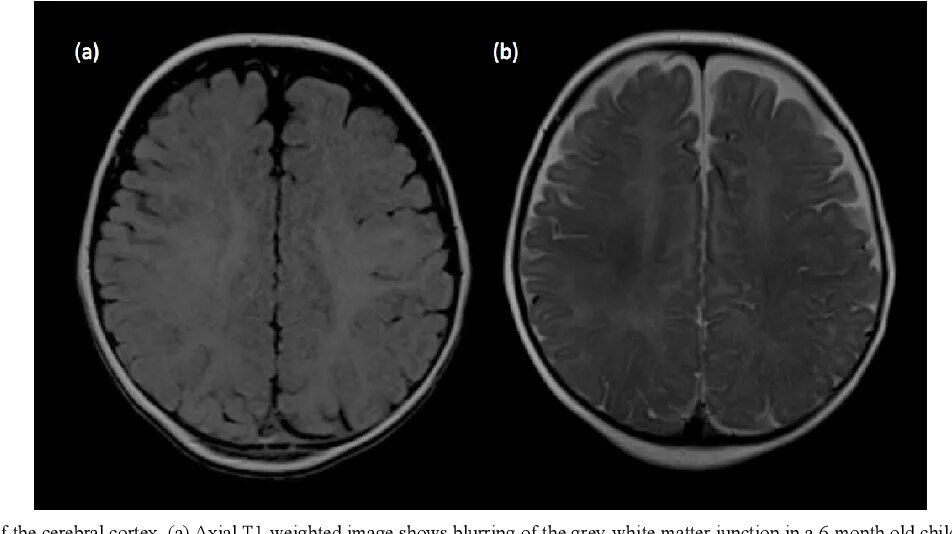

Normal abnormal